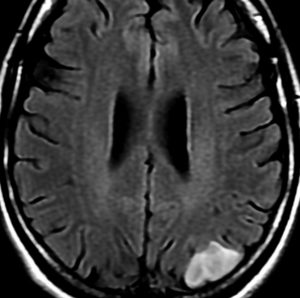

画像所見

• CTでは,低吸収域で周囲の脳より少し黒っぽく見えます

• MRI のT2・FLAIR(フレア)画像で淡く白く見える(高信号)のが特徴です

• 一般的には,びまん性で周囲がはっきりしない脳の中に「にじむような腫瘍」に見えます

• 初期には、一つの脳回に限局して境界が明瞭な小さな腫瘍として発見されることもあります (single gyrus glioma)

• ガドリニウム造影剤で増強されることはほとんどありません

• ガドリニウムで増強された場合はグレード3以上の星細胞系腫瘍が混じっていることを疑います

• 石灰化やのう胞はあり得るのですがとても稀です

• あった場合には乏突起膠腫を疑った方がいいでしょう

astrocytomaay1astrocytomaay3astrocytomaay2

左側頭葉のびまん性星細胞腫です。左側のT1強調ガドリニウム像ではほとんど腫瘍は見えません。真ん中のT2強調画像でも見づらいです。右側のフレア画像で白くにじんでいるところに腫瘍があります。どこまでが腫瘍の境界なのかがはっきりしない腫瘍です。左の海馬(記憶の中枢)を侵し,とてもゆっくり大きくなるタイプで,この患者さんは10年以上治療をしないで経過を見ています。全摘出できない星細胞腫グレード2です。